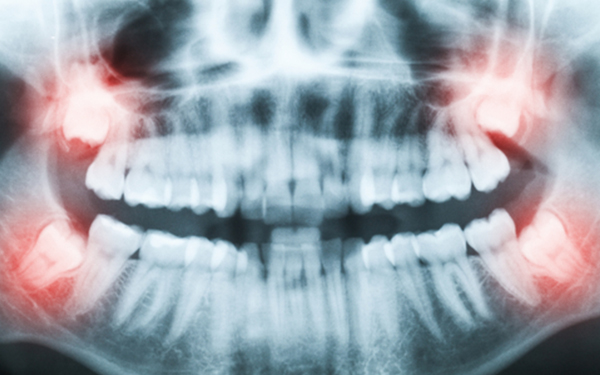

사랑니

Wisdom Tooth

사랑니는,

사랑니 크기에 비해 턱뼈의 공간이 부족한 경우, 사랑니가 올바르게

맹출할 수 없습니다. 이런 경우 사랑니가 누워서 맹출되거나 일부만

맹출되어 여러가지 문제를 야기할 수 있습니다.

사랑니를 발치해야 하는 경우